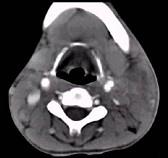

男性,67岁,颈部出现疼痛性肿块半年余,CT扫描如图所示,最可能的诊断是()A.神经鞘瘤B.囊肿C.淋巴结核D.淋巴瘤E.血管瘤

问题 男性,67岁,颈部出现疼痛性肿块半年余,CT扫描如图所示,最可能的诊断是()

选项 A.神经鞘瘤 B.囊肿 C.淋巴结核 D.淋巴瘤 E.血管瘤

答案 D